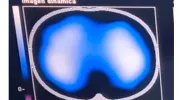

Imágenes de tomografía que se toman para analizar el desempeño de la fisioterapia con el incentivo de re-expansión pulmonar. El área de color azul-blanco representa el volumen del pulmón en un corte transversal, visto desde arriba, cuanto mayor aire llega a los pulmones se expande el pulmón y llega aire a zonas al pulmón que originalmente no se utilizaban.